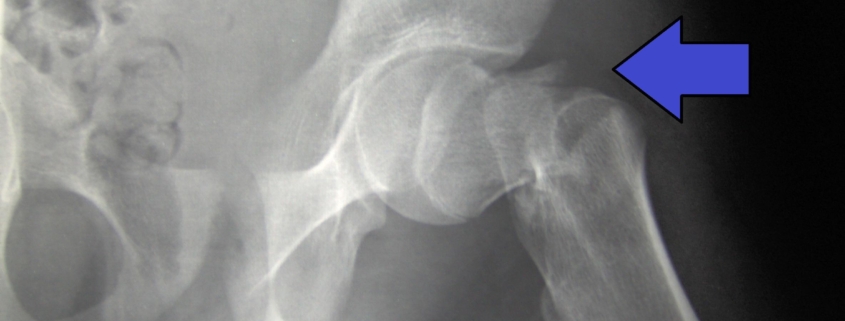

Hip fractures are common and serious injuries, especially among older adults due to falls. A healthy hip joint consists of a ball and socket, formed by the femur, or thighbone, and the pelvic bone. When the top of the femur or “neck of the hip” fractures, it’s often treated with compression fixation. This procedure stabilizes the fractured bone using metal screws, helping the fracture to heal.

A hip fracture is typically diagnosed through a combination of physical examination, X-rays, or other imaging tests like MRI or CT scan.